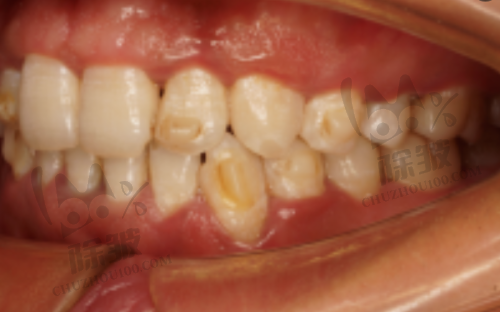

特别多在西安做过牙贴面的患者都分享了他们的成效感受。一些患者表示,做完牙贴面后,牙齿的外观有了较大的改善。原本发黄、有缺损的牙齿变得洁白整齐,整个人的魅力都提升了不少。比如一位姓张的女士,她之前因为牙齿发黄一直特别自卑,不敢开怀大笑。在西安美奥口腔做了全瓷牙贴面后,她的牙齿变得洁白如玉,笑容也变得更加灿烂了。她觉得牙贴面不仅让她的牙齿变得更美了,还让她变得更加自信了。还有一位李先生,他的牙齿有轻微的排列不齐,做了超薄树脂贴面后,牙齿看起来整齐多了。他说,虽然超薄树脂贴面的价格相对较低,但成效也特别不错,而且在日常生活中使用也没有什么问题。不过,也有部分患者反映,刚做完牙贴面后,会有一些轻微的不适感,比如牙齿敏感等。但这种情况一般会在一段时间后逐渐消失。

牙贴面是一种覆盖部分牙面的瓷或树脂等材料的修复体。它主要通过粘结技术,将人工修复体固定在患牙表面,以修复牙体的正常形态或改善其色泽。牙贴面的优点有特别多,首先它的磨除牙体组织少,对牙齿的损伤相对较小。与传统的烤瓷牙相比,牙贴面只需要磨除少量的牙齿表面组织,就能达到良好的美容成效。其次,牙贴面的美观度高,尤其是全瓷贴面,它的颜色和透明度与天然牙齿非常接近,几乎可以达到以假乱真的成效。另外,牙贴面的使用寿命也比较长,如果保养得当,可以使用10年甚至更长时间。不过,牙贴面也有一些缺点。比如它的价格相对较高,尤其是进口全瓷贴面;而且牙贴面的边缘可能会出现微渗漏的情况,导致牙齿出现继发龋等问题。所以,在做牙贴面之前,患者一定要充分了解牙贴面的优缺点,根据自己的实际情况做出选择。